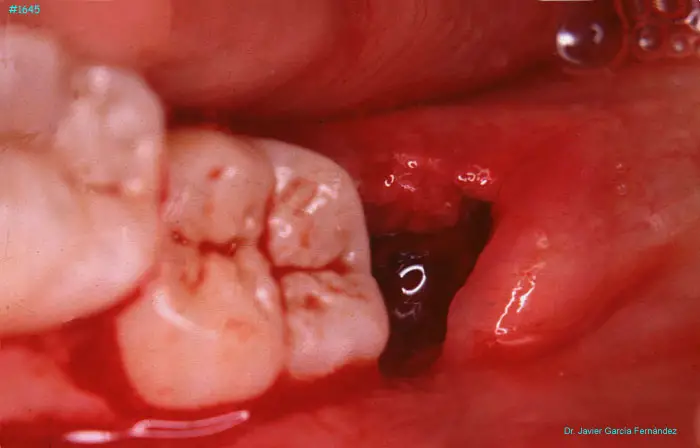

Atlas of Surgical Techniques in Periodontics. Chapter IV. Atlas de Técnicas Quirúrgica en Periodoncia

image 159